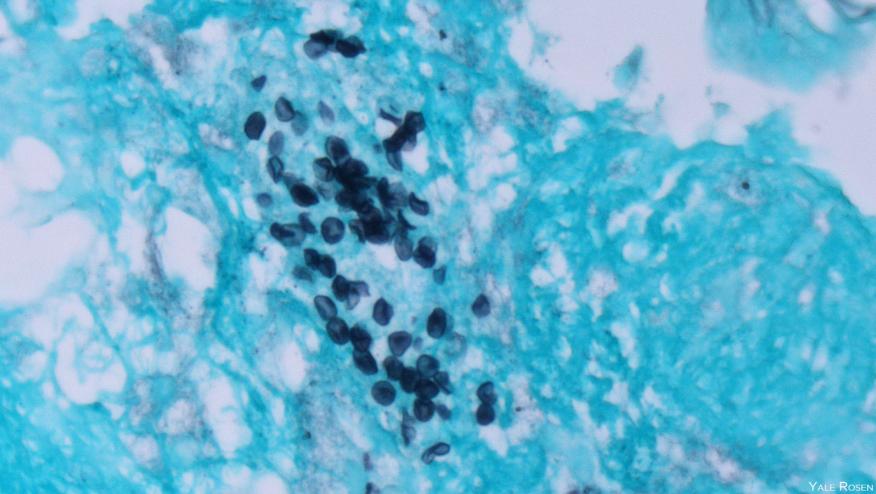

Among patients with dermatomyositis who were positive for the anti-melanoma differentiation-associated gene 5 antibody (MDA5), the prevalence of P. jirovecii pneumonia (PJP) was 7.5 per 100 person-years compared with only 0.7 per 100 person-years for those with MDA5-negative inflammatory myopathies (P<0.00001), said Qingran Yan, MD, and colleagues from Renji Hospital in Shanghai.

A total of 463 cases of inflammatory myopathy were included; during a median follow-up of 18 months, there were 14 cases of PJP. Patients with PJP differed significantly from those without the infection, in that 85.7% were anti-MDA5 positive versus 33% (P<0.0001), more often had interstitial lung disease (92.9% vs 70.4%), and had lower overall lymphocyte and CD4+ T lymphocyte counts. PJP patients also had higher erythrocyte sedimentation rates and ferritin levels, and had greater prednisone exposure.